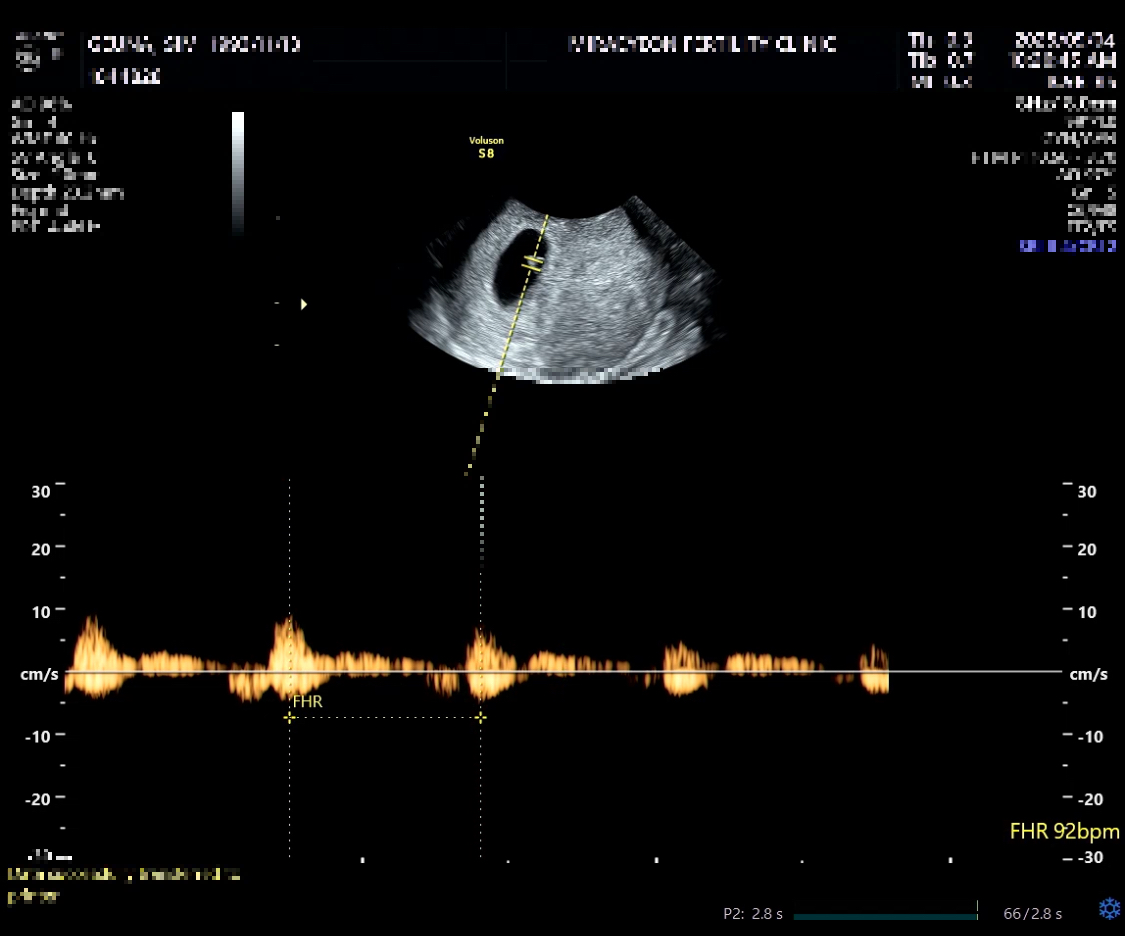

드디어 본 첫 초음파,,!!! 아기집, 아기, 난황, 심장소리까지 모두 보고 듣고왔어요!

선생님께서 모두 다 좋다고 하셔서,, 큰 걱정 없이 상담 마무리 하고 나왔어요.